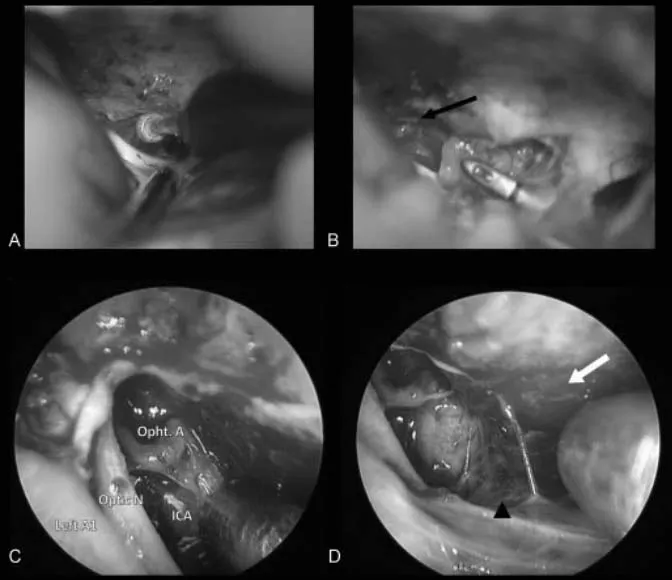

术中照片。(A)早期视神经减压术和管内肿瘤的暴露是通过磨除蝶缘和内侧视神经管来完成的。(B)直接切除肿瘤,同时识别和保护眼动脉(黑色箭头)。(C)内镜下直视神经管。(D)使用30度角内镜查看其它潜在的硬膜区域(白色箭头),如果发现,可以电凝处理。标注:ICA(颈内动脉)、Left A1(左大脑前动脉)、Opht.A(眼动脉)、Optic N(视神经)

最终,她来到福洛里希教授所在医院。先是对其病情做详细分析,根据肿瘤具体位置、大小、形态制定个体化手术入路。术中在内镜辅助下,采用经右额下入路肿瘤全切术,通过钻取蝶缘和内侧视神经管进行视神经减压术,再经额下入路为对侧交叉沟和视神经提供安全手术路径,在保障正常功能神经和脑组织不受损伤前提下,安全切除肿瘤。

视神经管的充分显露是肿瘤全切除的关键技术环节。通过在视交叉沟前肢进行精准磨骨操作,术者可完整显露视神经管内侧面。该磨骨区域的选择,可使术者以垂直于视神经长轴的视角进入管内空间,从而实现对伸入视神经管内肿瘤成分的完整暴露与切除。

需要特别指出的是,额下入路为对侧视交叉沟及对侧视神经提供了极佳手术轨迹。在直视条件下对视神经管内侧壁进行磨骨开窗时,术者可清晰观察视神经下内侧表面解剖结构与走行方向,在此保护条件下,可安全切除伸入视神经管内的肿瘤病灶,最大程度避免对视神经本体的机械性损伤及血供破坏。

福洛里希教授指出,内镜辅助技术在视神经管脑膜瘤手术中有不可替代的技术价值。内镜可清晰识别视交叉沟及鞍结节区域硬脑膜内微小浸润病灶,在视交叉沟前肢磨骨过程中及早发现蝶窦破损风险;同时,内镜能够有效拓展传统显微手术视野盲区,特别是视神经管深度区域等关键解剖位置。与传统显微手术相比,神经内镜可近距离抵达深部术区,术中视野清晰、立体感强,实现对肿瘤、周边血管、神经、脑组织等结构的精细观察,使解剖定位更加精确。肿瘤切除完成后,内镜可被置入瘤腔内部系统性检查肿瘤残余,从而实现对深部肿瘤切除范围的精细化控制,降低术后复发风险。